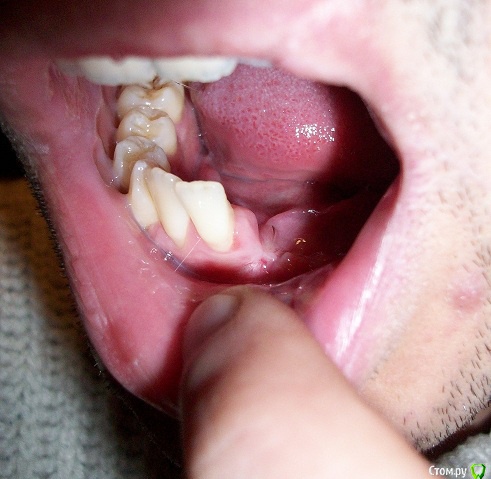

mikheil.osipov Опубликовано 16 декабря, 2015 Поделиться Опубликовано 16 декабря, 2015 Доброго времени сутокЧетыре месяца назад, 2-го августа, я попал в аварию и получил перелом нижней и верхней челюсти. На нижней челюсти был односторонний открытый перелом, а также перелом альвеолярного отростка с 1-го по 5-й зубы. Также был поврежден нерв, потеря чувствительности левой части губы и подбородка. Мне сделали операцию – на нижней челюсти провели остеосинтез титановой пластиной, альвеолярный отросток закрепили шинами, а на верхнюю наложили шов проволокой. По какой то причине нижняя челюсть пложо заживала, альвеолярная кость местами была оголена и даже был виден край ушка пластины, врач назначил солкосериловую мазь, один раз сделал пластику, но кость опять оголилась. Врачь сказал, что начался некроз (странно, но температуры и гноя не было) и 20 октября удалил отломонный отросток. После удаления прошло почти два месяца, 4 месяца после перелома, 6 декабря я снял томографию и вроде бы заживление идет нормально, но теперь у меня проблемы с дальнейшей имплантацией из-за недостатка костной ткани. Мне 25 лет и хотелось бы востановить утраченные зубы с учетом качества и долговечности. Возможно ли установить импланты и нужно ли для этого наращивание кости? Прошу подскажите какой будет оптимальный метод протезирования в моем случае? Ниже я выкладываю старую и новую 3D томографии и фото. Томография и фото до удаления:Ссылка на томографию: https://drive.google.com/open?id=0B4pglooYIfg_TXJSUXVEQ2p0b2c Последняя томография и фото:Ссылка на томографию: https://drive.google.com/open?id=0B4pglooYIfg_aVhLSHRobkZHdzA Заранее спасибо! Ссылка на комментарий

mikheil.osipov Опубликовано 17 декабря, 2015 Автор Поделиться Опубликовано 17 декабря, 2015 Так было до удаления: Вот панорама и снимки: Ссылка на КТ https://drive.google.com/open?id=0B4pglooYIfg_aVhLSHRobkZHdzA Я был на консультации и мне сказали что нужна пластика искуственной костью и каркасом. Также сказали, что верхние винты могут помешать при имплантации и их надо будет снять. Врачь сказал, что ситуация сложная, также недостаток мягких тканей создает проблемы. Возможно ли обойтись без каркаса? Ведь его установка и у даление дополнительная травма и есть риск осложнений. Возможно ли установить импланты более простым методом? Ссылка на комментарий